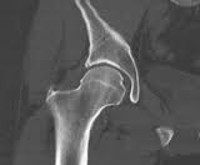

КТ тазобедренного сустава

Сканирование назначается пациентам с подозрением на развитие злокачественных или доброкачественных опухолей проксимального отдела бедренной кости, вертлужной впадины и окружающих мягких тканей. КТ тазобедренного сустава может обнаружить даже небольшие новообразования на доклинической стадии. Также метод эффективен при выявлении метастазов. Томографические исследования широко используются в травматологии, поскольку позволяют диагностировать переломы вертлужной впадины, головы и шеи бедра, в том числе - плохо просматриваемые на обычных рентгенограммах. С помощью КТ можно оценить степень повреждения кости, определить количество отломков, степень тяжести и направление смещения отломков и определить тактику лечения. Кроме того, компьютерная томография назначается пациентам до операции и после хирургического лечения перелома бедра, чтобы оценить эффективность вмешательства.

С помощью КТ можно выявить инфекционные процессы - артрит, остеомиелит. Этот метод диагностики очень информативен и при подозрении на дегенеративно-дистрофические изменения в суставах. Сканирование назначено пациентам с остеопорозом, остеопорозом. Слоистые изображения патологического очага позволяют оценить степень поражения и, основываясь на этих данных, определить последующую схему лечения. Это один из наиболее информативных методов диагностики врожденных аномалий строения этого сустава. КТ показана при подозрении на врожденный вывих бедра и дисплазию бедра. Техника также используется при болезни Пертеса, патологии, которая развивается в контексте нарушения в кровотоке и приводит к асептическому некрозу головки бедренной кости. Чтобы оценить функционирование кровеносных сосудов и состояние сустава в целом, удобнее выполнять сканирование с введением контрастного вещества.

При сравнении компьютерной томографии и магнитно-резонансной томографии следует отметить, что оба метода могут использоваться для получения изображений исследуемой области слой за слоем. В то же время МРТ более информативна при обследовании мягких тканей, а КТ предоставляет информацию о состоянии костных структур. Магнитно-резонансная томография использует электромагнитное излучение, которое не ставит под угрозу здоровье пациента, поэтому процедуру можно повторять столько раз, сколько необходимо. КТ тазобедренного сустава разрешается максимум два раза в год. Менее значимым исследованием по сравнению с КТ является стандартная рентгенография, которая позволяет делать снимки, на которых исследуемые структуры перекрываются. С помощью КТ врач может создать трехмерную модель сустава на основе многослойных изображений.